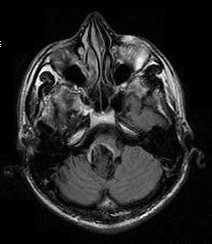

КТ/МРТ:

Обычно обнаруживают объемное образование в дне IV желудочка, часто с окклюзионной гидроцефалией.

Рентгенологически может быть трудно отличить от медуллобластомы, могут помочь следующие признаки:

1. Калицификаты часто встречаются в эпендимомах, но редко (<10%) в медуллобластомах

2. Медуллобластомы обычно возникают из крыши IV желудочка (из его вершины, фастигиума), который покрывает опухоль («симптом банана»), эпендимомы имеют тенденцию врастать в IV желудочек со дна

3. Эпендимомы имеют негомогенную структуру на МРТ в Т1 режиме

4. Экзофитный компонент в эпендимомах имеет тенденцию давать высокий сигнал на МРТ в Т2 режиме (у медуллобластом он только немного гиперинтенсивный)

Эпендимома составляет 2-9% от внутричерепных опухолей и 6% от глиом. Из эпендимальных опухолей у взрослых встречается субэпендимома. Она составляет около 8% от эпендимальных опухолей и располагается у стенки желудочка. Пики частоты собственно эпендимомы приходится на возраст 5 лет и 34 года. Опухоль происходит из эпендимоцитов. Обычно это доброкачественные формы. В 60-70% случаев опухоль локализуется инфратенториально в области IV желудочка и в 5-8% в полушариях мозжечка. Гораздо реже обнаруживается супратенториальная локализация эпендимомы: в полушариях вблизи желудочков (на корональных срезах по виду напоминает “цветную капусту”), в области III желудочка, четверохолмия или мосто-мозжечковом углу. Доброкачественные эпендимомы имеют экспансивный тип роста. Внутренняя структура при МРТ неоднородная в связи с кистами (43-83% случаев) и кальцификацией (50% случаев). Контрастное усиление при МРТ наблюдается в трети случаев. Анапластическая эпендимома (градация III) метастазирует по ликворным путям.

Инфратенториальные эпендимомы у взрослых встречаются гораздо реже, чем у детей. Эпендимома встречается в области IV желудочка. Она имеет солидный и кистозный компоненты. При МРТ головного мозга их внутренняя структура часто неоднородная за счёт кальцинатов, кист, гемоглобина и гемосидерина, а также внутриопухолевых сосудов. Эпендимомы часто распространяются через отверстия Лушка и Маженди, что видно при МРТ в корональной плоскости. профессор Холин А.В. имеет большой опыт МРТ в СПб диагностики внутрижелудочковых опухолей мозга в том числе и на открытом МРТ. Среди центров МРТ СПб мы имеем огромный опыт МРТ выявления разных опухолей головного мозга.

МРТ головного мозга. Анапластическая эпендимома коллатерального треугольника левого бокового желудочка (стрелка). Аксиальные Т2-зависимая, Т1-зависимая и Т1-зависимая с контрастированием МРТ.